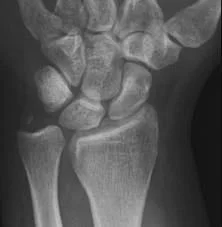

- Examine the wrist:

- For disruption of the distal radio-ulnar joint

Colle’s Fracture

- Extra-articular fracture of the distal radius with dorsal and radial displacement of the wrist “Dinner fork” deformity

- Seen in elderly with osteoporosis

- Caused by falling on the outstretched hand